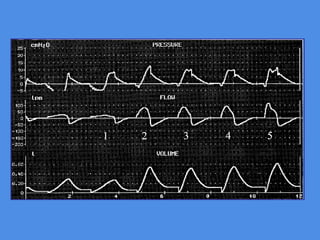

-Ineffictive triggering at

30 l/mn

- Increase in flow rate

- Subsequent increase of

expiratory time

- Decreased dynamic

hyperinflation

- Subsequent decrease

in ineffictive trigerring

Importance of flow pattern

Increase in peak-flow setting fron 60 to 120

l/mn eliminated scooped appearance of the

airway pressure waveform